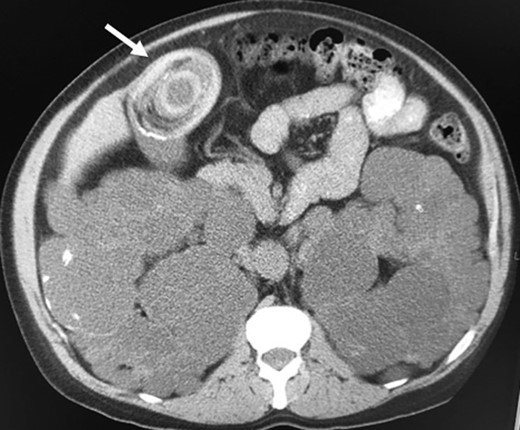

A 73-year-old male patient presented to the emergency room (ER) with vomiting, abdominal pain and bloody diarrhea. His past medical history includes arterial hypertension, coronary artery disease, peripheral vascular disease, polycystic kidney disease, end-stage renal disease and superior vena cava thrombosis on warfarin therapy. His surgical history includes an abdominal aortic aneurysm repair and a right nephrectomy. Seven months prior to the events, the patient was admitted for acute calculous cholecystitis and cholangitis that were managed with sphincterotomy and choledocolithiasis extraction via endoscopic retrograde cholangiopancreatography, followed by percutaneous cholecystostomy. It is worth noting that a large gallstone was present in the gallbladder when the patient has undergone an abdominopelvic CT scan 9 years prior to the current episode for an unrelated condition (Fig. 1).

Giant gallstone located in the gallbladder on abdominopelvic CT scan.